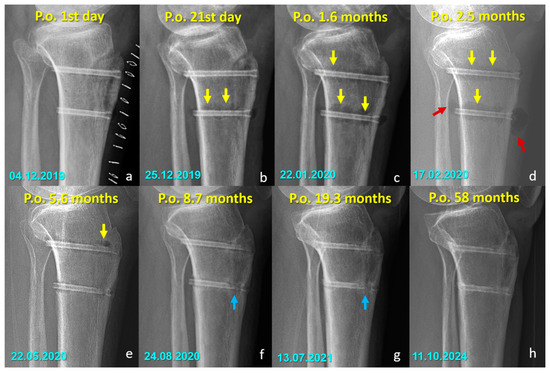

Radiographic Findings in the Mg Screw Group